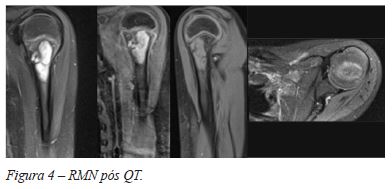

Após completar quimioterapia neo-adjuvante, a doente foi submetida a uma Tomografia computorizada (TC) pulmonar de controlo que mostrou a manutenção dos micronódulos pulmonares bilaterais milimétricos. A RM de controlo revelou uma diminuição da lesão no seu maior eixo (5,6 cm), com aparente preservação da fise em toda a sua extensão, excepto num único ponto (Figura 4). Verificou-se uma redução evidente do edema medular e desaparecimento da skip lesion, concluindo-se que esta corresponderia a uma provável extensão do edema medular prévio, dado que não apresentava hipossinal em ponderação T1. Contudo, a massa de tecidos moles parecia envolver o nervo axilar.